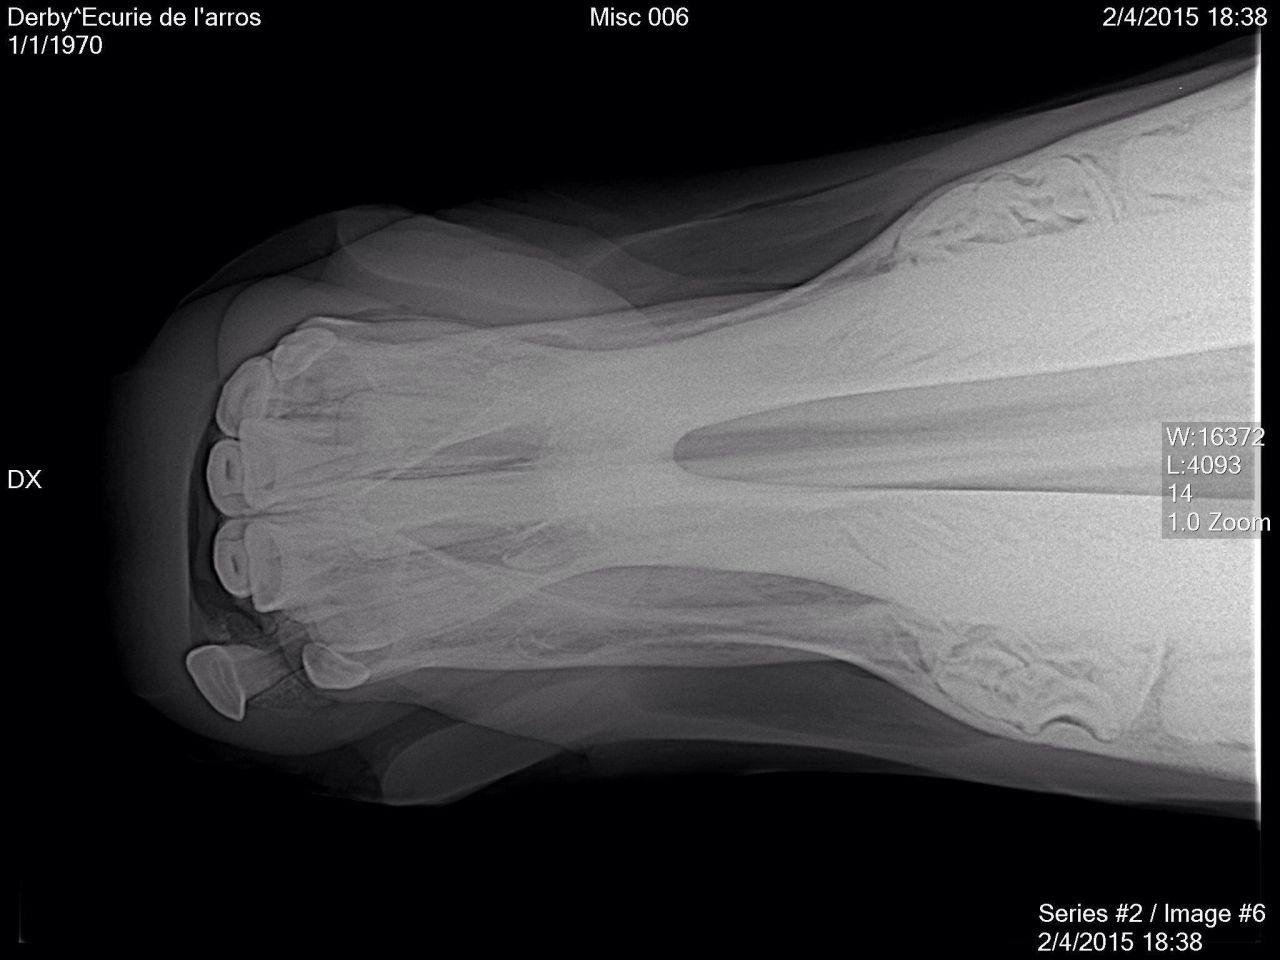

| Dire merci | Tout d abord desolee de ne pas vous avoir donné des nouvelles plus tôt . Le loulou va parfaitement bien, la dent etait bien fracturée, un cerclage a été réalise par l ecole veto de Nantes. Il est resté en place 6 semaines avant d être enlevé. Aujourdhui il est de nouveau au pré avec ses copains et tout va pour le mieux pour lui. Voici quelques photos: ![]() [/url] |

Par playboy78 : le 22/04/15 à 14:03:05

| Dire merci | ![]() [/url] ![]() [/url] ![]() [/url] ![]() [/url] ![]() [/url] |

| Dire merci | Et une fois le cerclage réalisé, l intervention a duré 2 bonnes heures, le chirurgien a beaucoup gratté la gencive pour pouvoir remettre la dent à sa place. Le travail realisé est vraiment superbe, on ne se rend aujourdhui quasiment plus compte de ce qui lui est arrivé.![]() [/url] |